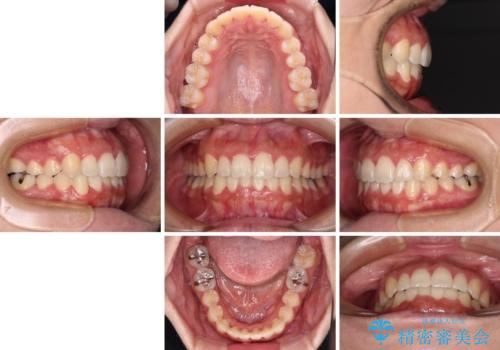

前歯のデコボコをインビザラインでスッキリと

- 上下前歯のデコボコを気にして来院された患者様です。

デコボコを解消する過程で、歯列の拡大により口元が突出する可能性があったため、4本の親知らずを抜歯しておき、歯列全体が後方に移動するように設計し、インビザラインにて矯正治療を行うこととしました。

日々の装着時間をしっかりと守って治療の臨んでくださったため、治療前のシミュレーションに近い形で矯正治療を進めて行くことができました。